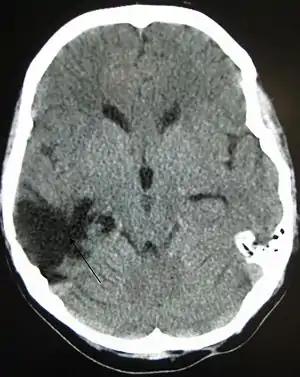

One type of focal injury, cerebral laceration, occurs when the tissue is cut or torn.[37] Such tearing is common in orbitofrontal cortex in particular, because of bony protrusions on the interior skull ridge above the eyes.[31] In a similar injury, cerebral contusion (bruising of brain tissue), blood is mixed among tissue.[22] In contrast, intracranial hemorrhage involves bleeding that is not mixed with tissue.[37]

Hematomas, also focal lesions, are collections of blood in or around the brain that can result from hemorrhage.[10] Intracerebral hemorrhage, with bleeding in the brain tissue itself, is an intra-axial lesion. Extra-axial lesions include epidural hematoma, subdural hematoma, subarachnoid hemorrhage, and intraventricular hemorrhage.[38] Epidural hematoma involves bleeding into the area between the skull and the dura mater, the outermost of the three membranes surrounding the brain.[10] In subdural hematoma, bleeding occurs between the dura and the arachnoid mater.[22] Subarachnoid hemorrhage involves bleeding into the space between the arachnoid membrane and the pia mater.[22] Intraventricular hemorrhage occurs when there is bleeding in the ventricles.[38]